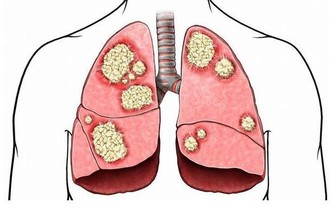

83.【肺癌】:半枝蓮30克,白石英30克。水煎服,每日一劑。

86.【肺結核:】活烏龜一隻,用泥包住,用暗火,慢火燒焦去泥,研成龜粉,開水沖服,每天三次,每次一錢,效果良佳,一百日即愈.(忌狗肉酸辣食物)。

89.【肺氣腫:仙人掌】2兩,去皮切片,香油炸黃,加水一碗,燒開七次,剩半碗即可,每日暮途窮3次,7天痊癒。

91.【肺炎】:魚星草一把,燉七個荷包雞蛋吃,每日一次,十天愈。

106.【肺結核】,氣管炎:羊肉500克,小麥仁(小麥去皮)60克,生薑9克,熬燉成稀粥,每天早晚各服一次,連服一月痊癒。